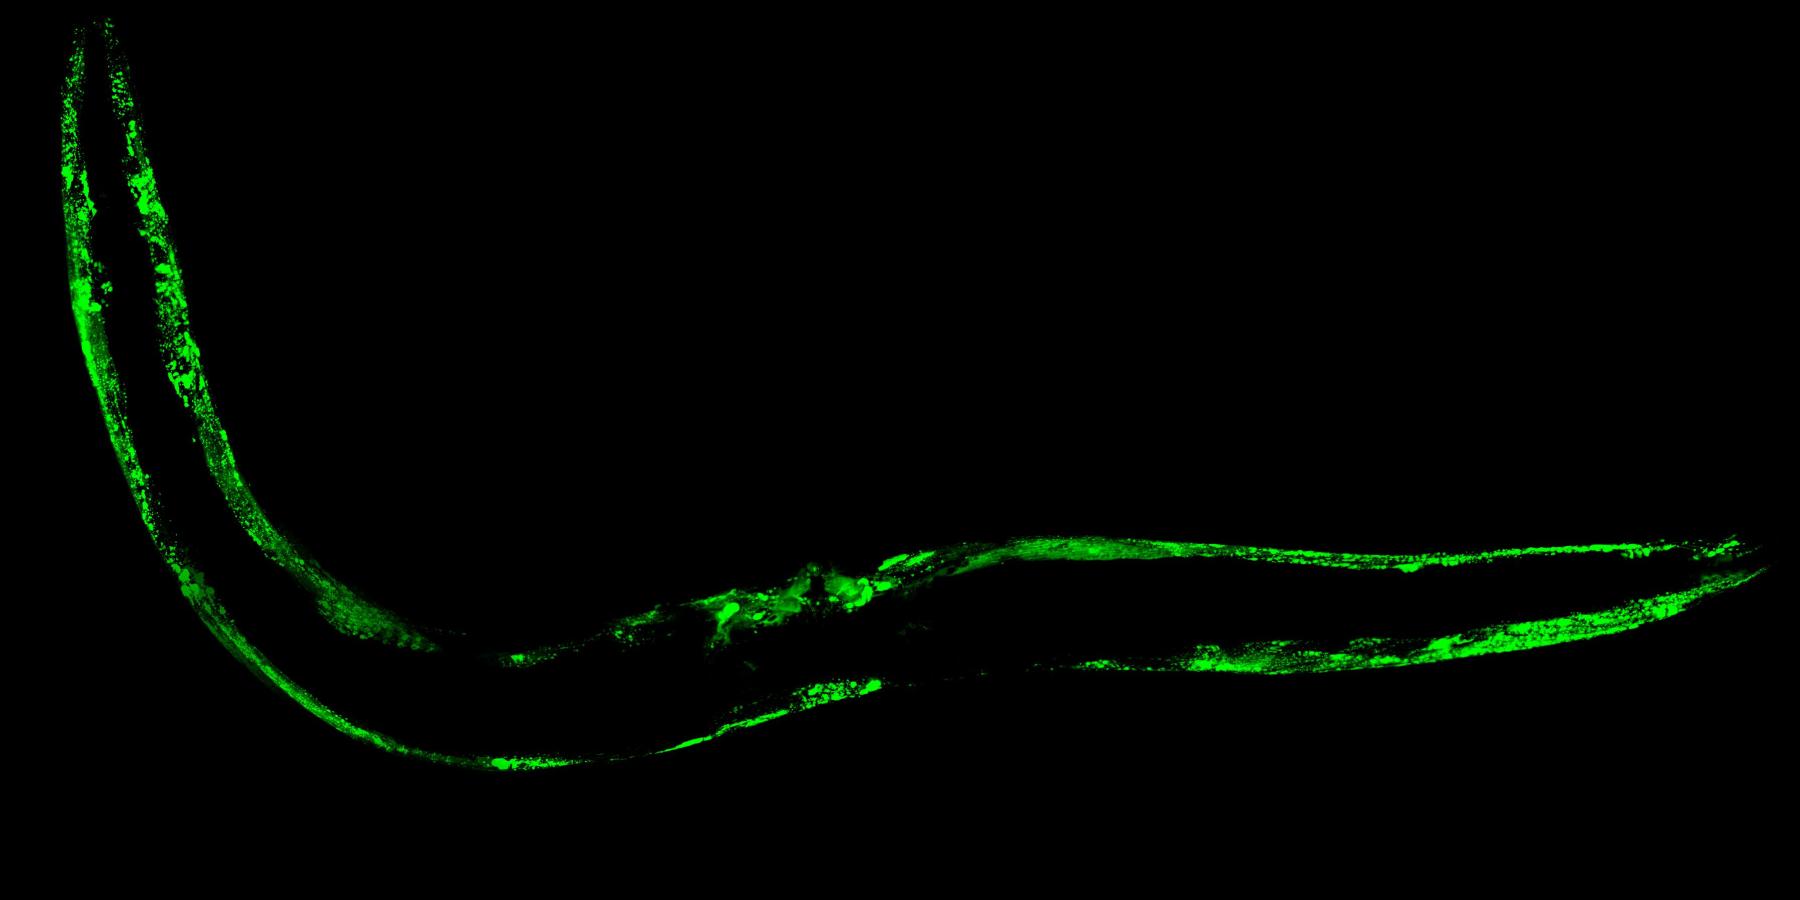

As part of the Koski Family University Fellowship, I conducted research on neurodegeneration using the nematode worm C. elegans as a model to study α-synuclein aggregation, which is associated with Parkinson’s disease. Over the course of the summer, I developed an imaging and analysis workflow involving confocal microscopy, fluorescence imaging, and quantitative assessment using ImageJ and RStudio. I tested the effect of a mannitol-based treatment on α-synuclein aggregation by imaging worms at multiple time points (days 1, 7 and 14 of adulthood) and quantifying aggregate size, count, and fluorescence intensity relative to worm size. Mannitol is a sugar alcohol compound that has shown potential as a therapeutic agent due to its ability to inhibit protein aggregation and transiently open the blood-brain barrier. I also helped refine protocols for nematode growth plate preparation and live worm imaging, gaining experience in both wet lab techniques and data processing. This project deepened my interest in translational neuroscience and taught me how to design, troubleshoot, and analyze an independent experiment from start to finish.